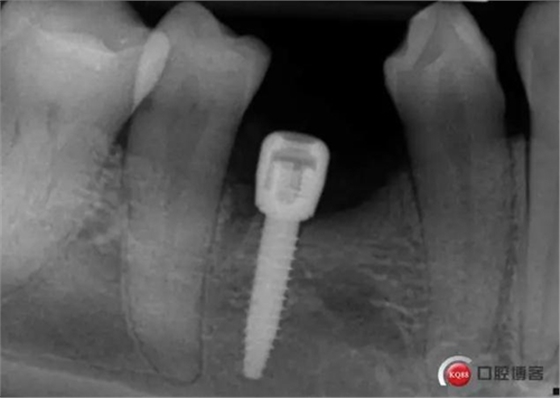

三個(gè)月后上基臺(tái)

牙冠